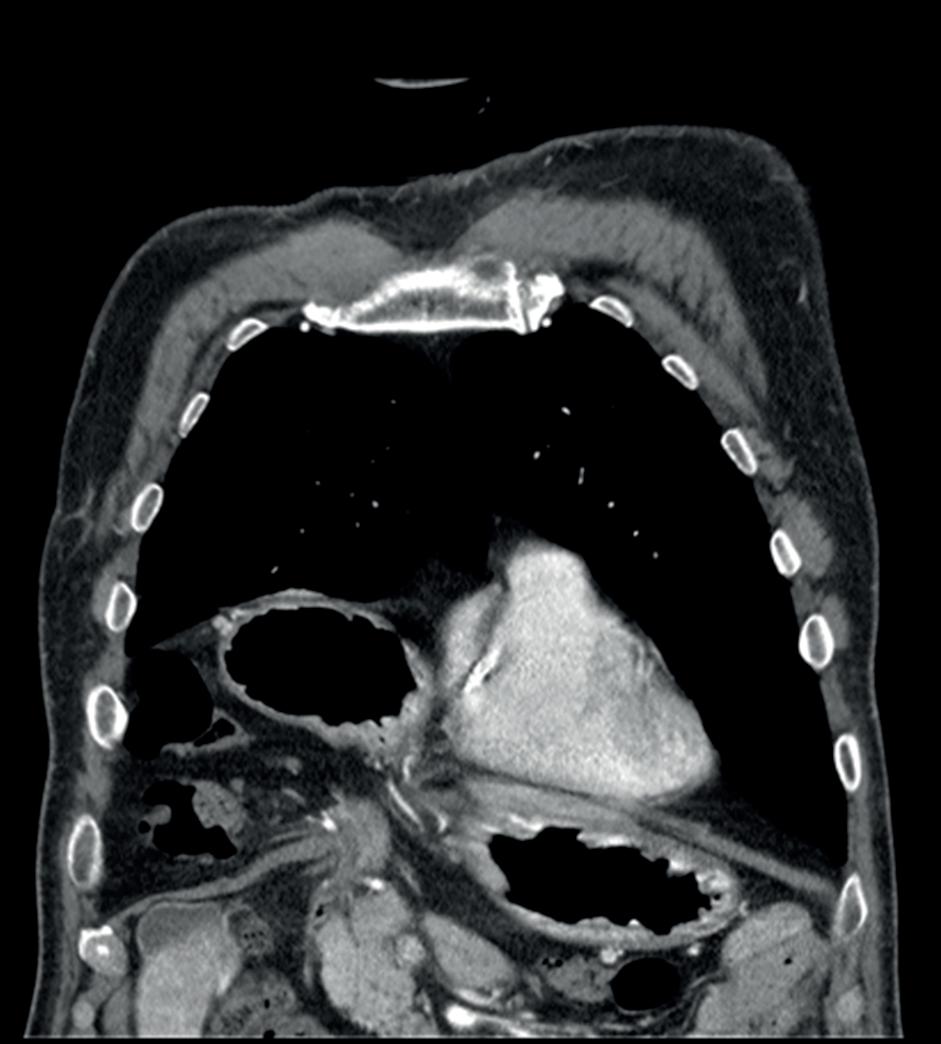

Forekomsten er 1 til 4 av 10.000 fødte (figur 1).

FIGUR 3: CT-bilde av en pasient med et Morgagni hernie hvor tarm og ventrikkel har herniert opp i høyre torakshule. FIGUR 1: Oversikt over medfødte diafragmahernier. IVC = Inferior Vena Cava. FIGUR 2: CT-bilde av en pasient med et Bochdalek hernie hvor tynntarm, kolon og ventrikkel har herniert opp i venstre thorakshule og fyller store deler av denne.